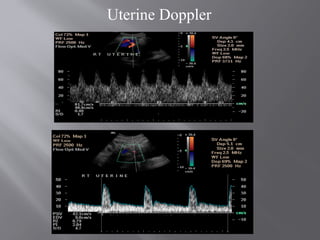

Uterine Doppler

Umbilical Doppler